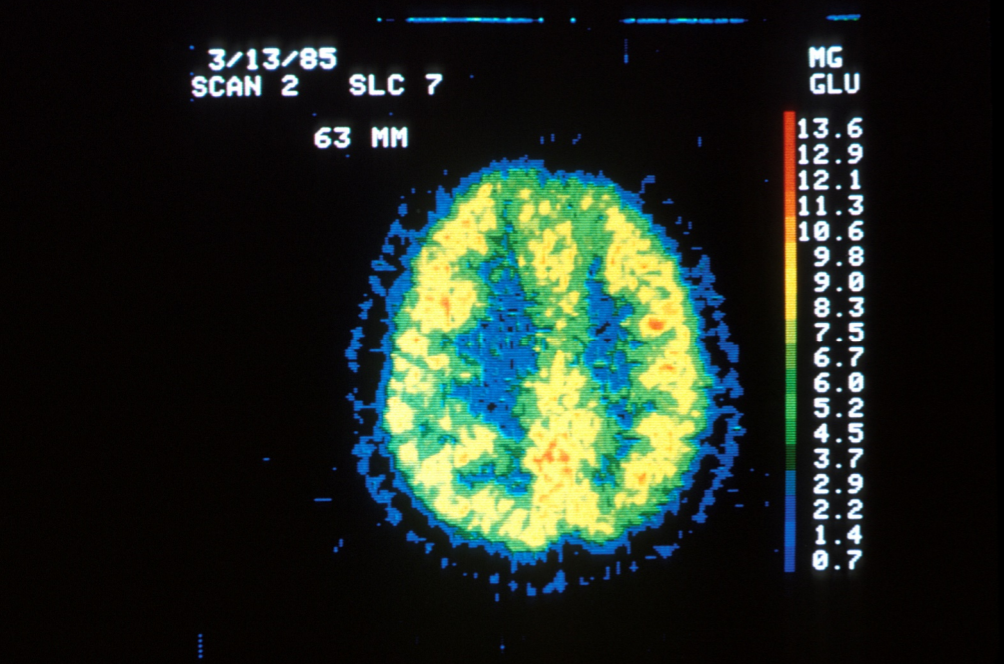

Ciekawą symulację opublikowało czasopismo „Psychological Science” (Stephen Chew). Do zilustrowania tego mitu wykorzystano rzeczywisty skan mózgu, wykonany przy użyciu PET (pozytronowej tomografii emisyjnej, dzięki której możemy zobaczyć – w dużym uproszczeniu – ile glukozy zużywają poszczególne obszary mózgu).

Źródło: „Psychological Science”

Trzecie zdjęcie z kolei przedstawia skan mózgu osoby, która leżała w skanerze, nie wykonując żadnej aktywności. Widać na nim obraz zdrowego mózgu, na którym każdy fragment tkanki zużywa glukozę, czyli jest aktywny.

Podsumowując – niepodważalnym faktem, potwierdzonym licznymi badaniami, jest to, że używamy 100% mózgu. Nawet gdy śpimy, jest on aktywny i czuwa nad utrzymaniem podstawowych procesów fizjologicznych. Potwierdzają to zarówno publikacje pokazujące bezpośrednio zużycie glukozy czy tlenu przez komórki, jak i obecne w mózgu mechanizmy, które pośrednio wskazują, że niemożliwe byłoby utrzymanie 90% nieużywanego organu.